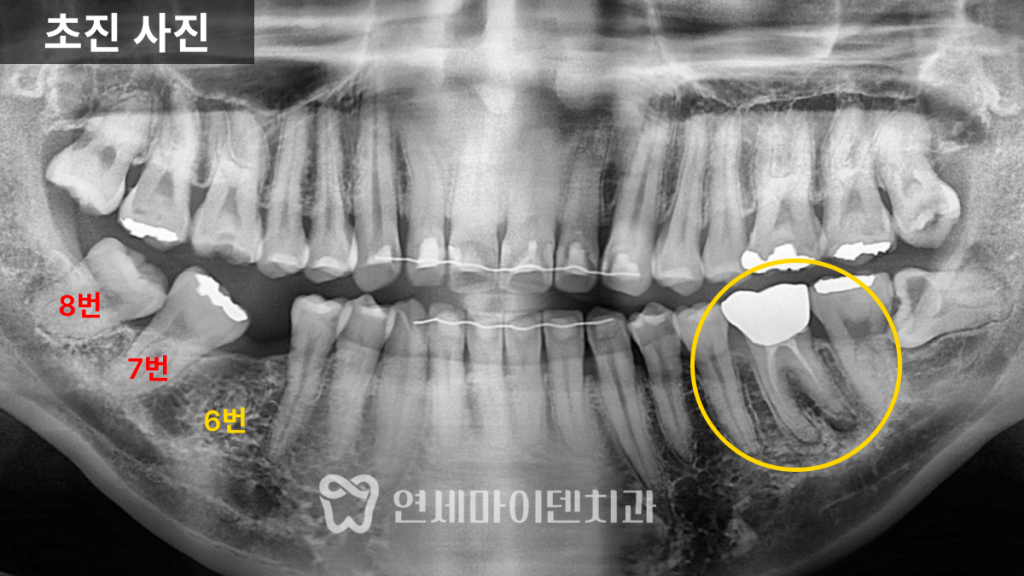

치아교정·임플란트 협진 케이스를 설명드리겠습니다.초진 상태

초진 파노라마 사진에서

오래전 6번 어금니가 발치된 상태였습니다.그 뒤쪽에 있던 7번, 그리고 사랑니가

앞쪽으로 상당히 많이 쓰러져 있었습니다.

원래 6번과 7번은

크기가 거의 비슷해야 하는데,쓰러지면서

임플란트가 들어가야 할 공간이

앞 치아보다도 더 좁아진 상태였습니다.이 상태에서 임플란트를 바로 진행하면